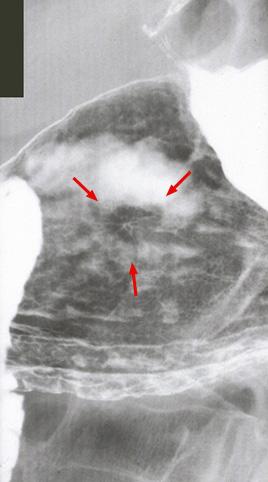

疾病(病理主体)的分类恶性上皮性肿瘤/腺癌

部位(按器官分)胃(部位)/体部

检查方法X线

肿瘤的肉眼分类0型(表在型)/IIc型(IIc)

肿瘤最大直径1~9

肿瘤的深度m